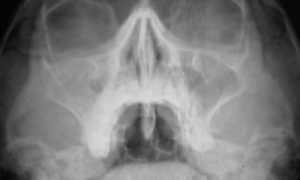

Рентген.

На снимке можно увидеть уровень жидкости в лобной пазухе. С помощью рентген снимка проводят дифференциальную диагностику негнойного фронтита от гнойного.